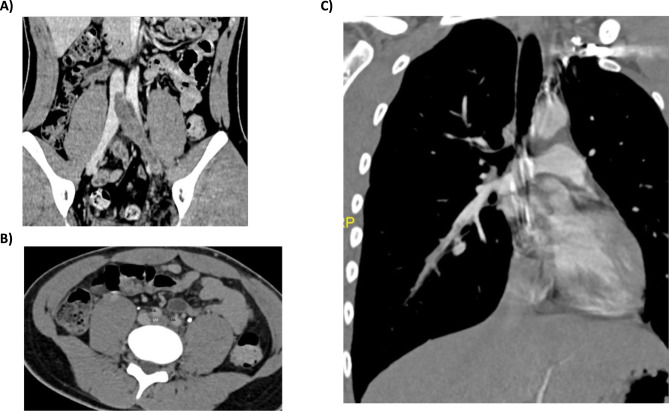

Combined thrombophilia represents 7.8-8.3% of the patients with thrombophilia and confers a higher risk for thrombosis development and recurrence. Here, we present a 17-year-old boy carrier of three congenital thrombophilias, two severe (type I antithrombin deficiency and type I protein S deficiency) and one prothrombotic polymorphism (prothrombin G20210A), all in heterozygosis. He developed an extensive deep venous thrombosis in lower left limb, reaching proximal inferior vena cava and contralateral iliac vein, in the setting of prolonged rest. Endovascular therapy with local thrombolytic agent infusion followed by mechanical thrombectomy was performed, achieving a favorable clinical and radiological evolution. Antithrombin replacement to achieve levels between 80% and 120% with heparin administration was used during the endovascular procedure. The patient is currently asymptomatic and maintains indefinite anticoagulation with warfarin, keeping an appropriate anticoagulation range (international normalized range between 2.5 and 3.5).

合并血栓性疾病患者占血栓性疾病患者的 7.8%-8.3%,血栓形成和复发的风险较高。这里,我们要介绍的是一名 17 岁男孩,他患有三种先天性血栓性疾病,其中两种为重度(I 型抗凝血酶缺乏症和 I 型蛋白 S 缺乏症),一种为凝血酶原多态性(凝血酶原 G20210A),均为杂合型。在长时间休息的情况下,他的左下肢出现了广泛的深静脉血栓,血栓到达下腔静脉近端和对侧髂静脉。患者接受了局部溶栓的血管内治疗,随后进行了机械性血栓切除术,临床和影像学结果良好。在血管内治疗过程中,使用了抗凝血酶替代物,使肝素水平达到 80% 至 120%。患者目前没有任何症状,仍在使用华法林进行无限期抗凝,并保持适当的抗凝范围(国际正常化范围在 2.5 至 3.5 之间)。